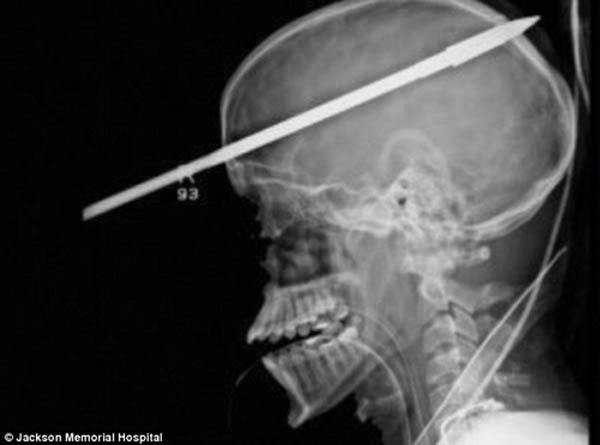

少年被46公分长捕鱼枪射穿头颅奇迹生还【图

少年被捕鱼枪射穿头颅奇迹生还

少年被捕鱼枪射穿头颅奇迹生还[组图]

少年被捕鱼枪射穿头颅奇迹生还[组图](5)